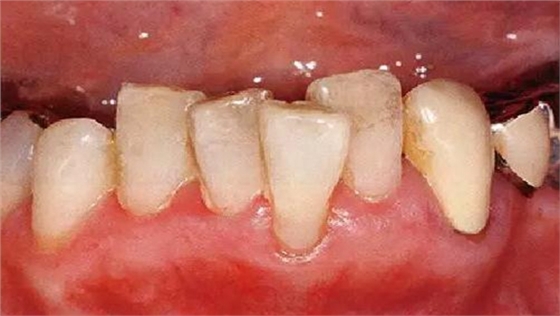

●牙列異常引起的附著喪失

牙列不齊導(dǎo)致被擠出牙弓的牙齒,其牙槽骨、牙齦變薄,很容易引起附著喪失、露出根面。由于刷牙過(guò)度會(huì)進(jìn)一步引起牙齦萎縮、根面磨耗、根面齲、牙周炎惡化,需要格外注意(本案例中,牙頸部已經(jīng)做過(guò)充填處置)。